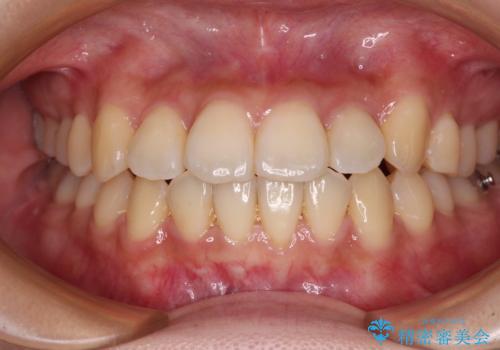

【モニター】前歯のデコボコを改善 ワイヤー矯正を併用したインビザライン矯正

舌側転位している側切歯特有の、切縁の位置が不揃いであったり、根元が内側に引っ込んだ状態であったりという、インビザライン独特の仕上がりになることなく、きれいに整った歯列とすることができました。